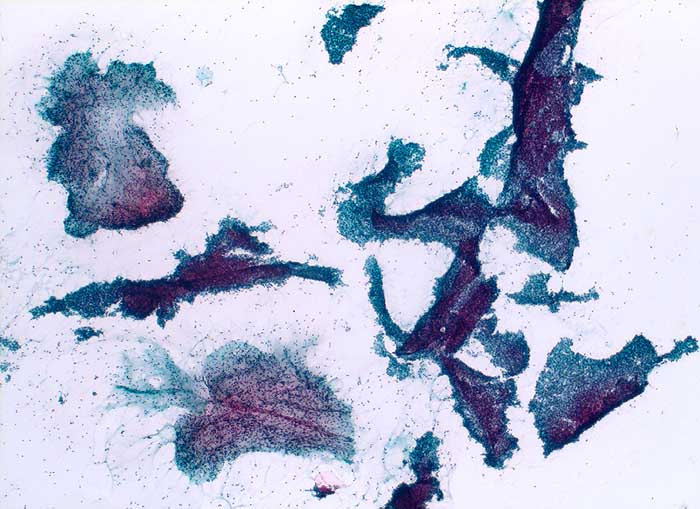

Feinnadelpunktion Mamma: Zahlreiche grosse, teils stark verzweigte und breite Verbände von regelrechten duktalen Epithelien. Im Ausstrichhintergrund zahlreiche bipolare nackte Kerne und immer wieder myxoides Stroma.

Histologische Diagnose: Fibroadenom mit ausgeprägtem Stromaödem

Zytologische Diagnose: Fibroadenom / phylloider Tumor

630